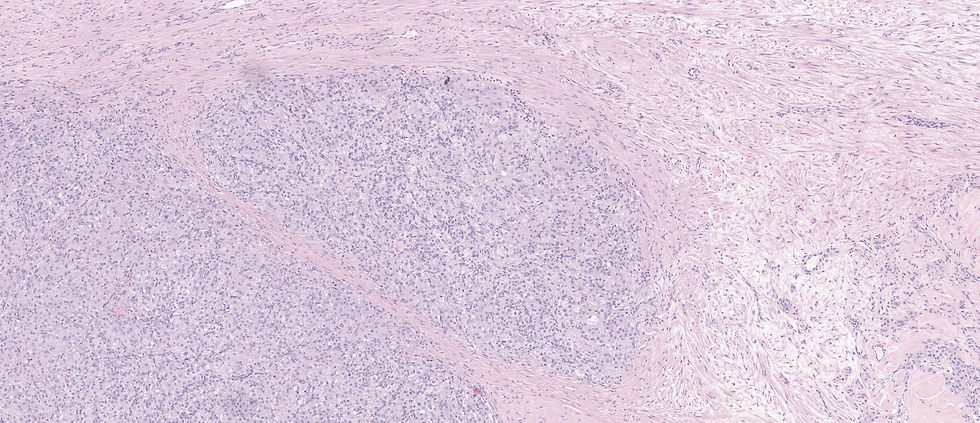

The correct answer is E. This is a classic case of sclerosing stromal tumor: 1) alternating cellularity 2) pseudo-lobular appearance 3) thin walled dilated staghorn vessels. The pseudolobules in a myxoid, edematous, or collagenous stroma is characteristic.